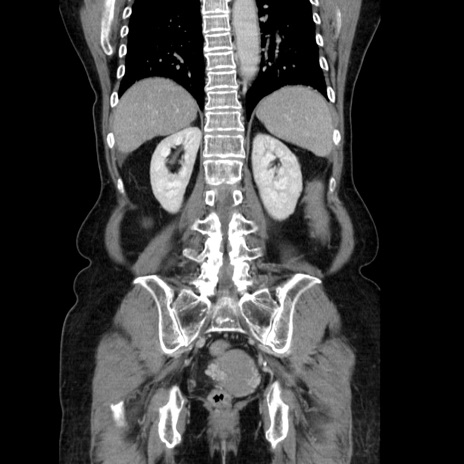

症例5(冠状断像)

【症例】70歳代女性

【主訴】お腹が張る

【現病歴】1週間くらい前から腹部膨満の自覚あり。昨日夜から増悪したため、本日救急外来受診。

【身体所見】意識清明、BT 36.5℃、BP 165/106mmHg、HR 80bpm、SpO2 98%、腹部:膨満、軟、自発痛・圧痛なし、触診にて不快感あり、腸蠕動音:減弱

【データ】WBC 12600、CRP 1.04